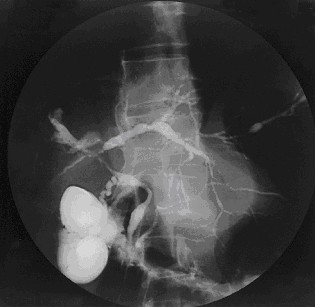

• Classic ‘beads-on-a-string’ appearance with the string being areas of narrowing/strictures and the beads being the normal or slightly dilated duct.

• This is seen for intra-hepatic and extra-hepatic ducts.

Joy Worthington, Roger Chapman, CC BY 2.0 , via Wikimedia Commons

Cholangiogram of PSC